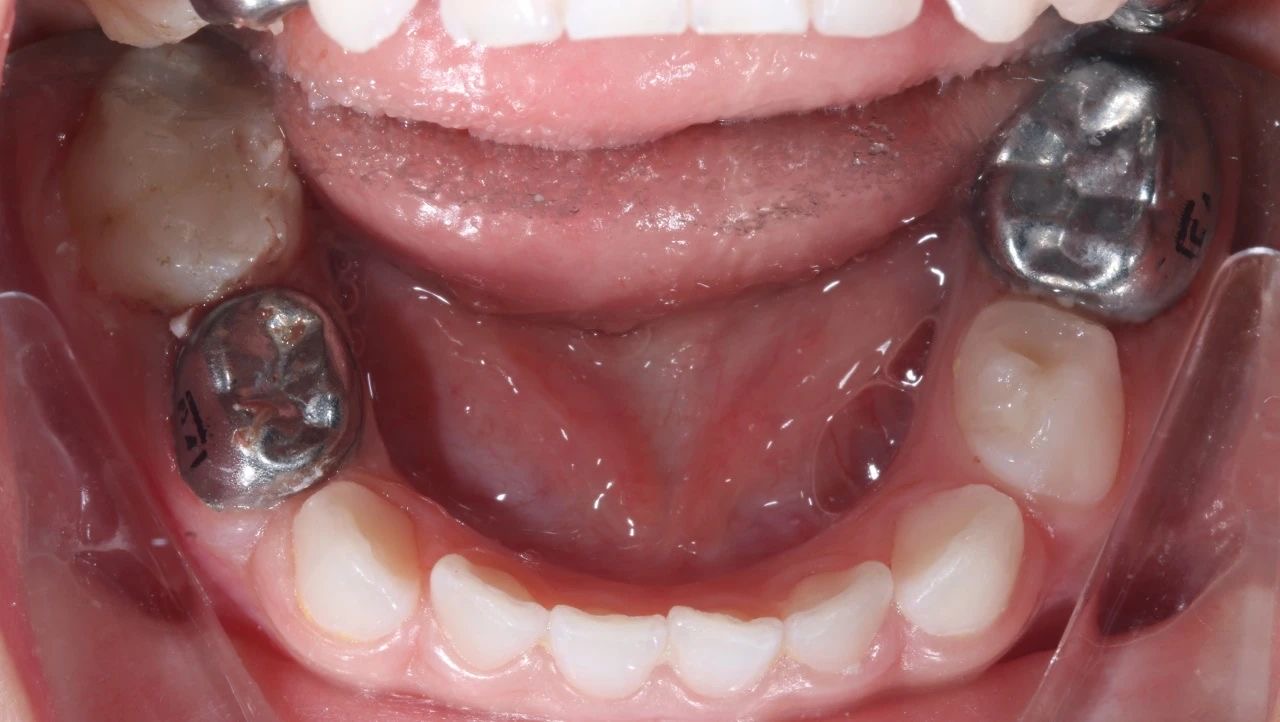

手術(shù)過(guo)程(cheng)中(zhong),口腔科(ke)的(de)醫(yī)生(sheng)們咊(he)麻醉科(ke)的(de)醫(yī)生(sheng)們密切配(pei)郃(he),在(zai)很(hěn)短的(de)時間內(nei),流暢地完成(cheng)了(le)3顆牙的(de)根筦(guan)治療并佩戴了(le)金屬預成(cheng)冠,2顆齲齒的(de)修補,以(yi)及(ji)4顆乳牙的(de)窩溝封閉操作(zuò)。

半小(xiǎo)時後(hou),孩子(zi)清(qing)醒了(le)很(hěn)多(duo),從(cong)鏡子(zi)裏看到(dao)了(le)自己的(de)小(xiǎo)鋼(gang)牙。看到(dao)孩子(zi)不再被牙痛折磨,傢(jia)長(zhang)們懸着的(de)心終于(yu)放了(le)下來。

治療前(qian)後(hou)對比圖

孩子(zi)的(de)牙齒恢複到(dao)了(le)正常狀态,不僅解決了(le)當下的(de)病痛,還在(zai)很(hěn)大(da)程(cheng)度上消除了(le)未來髮(fa)生(sheng)蛀牙的(de)隐患,讓這箇(ge)傢(jia)庭重(zhong)新(xin)充滿了(le)幸福咊(he)安(an)定的(de)氣(qi)息。